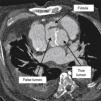

A 68-year-old man with a history of systemic hypertension and chronic renal failure was admitted to our emergency department with chest pain and dyspnea. He had undergone tube graft replacement of the ascending aorta due to an acute type A aortic dissection 10 years previously. On admission he was hypertensive and tachycardic with a continuous murmur at the left upper sternal border. The electrocardiogram revealed nonspecific repolarization abnormalities and the transthoracic echocardiogram showed a severely dilated aortic root with an intimal flap and continuous turbulent flow from the aortic root toward the right ventricle (Figures 1 and 2). There was moderate aortic regurgitation caused by poor leaflet coaptation. The right chambers were slightly dilated and both ventricles had normal systolic function. Chest computed tomography confirmed aortic root dissection with a fistula between the aortic false lumen and right ventricle (Figures 3 and 4). The coronary arteries were not involved. The patient was rejected for surgery due to very high surgical risk and died a few days later after sudden hypotension.